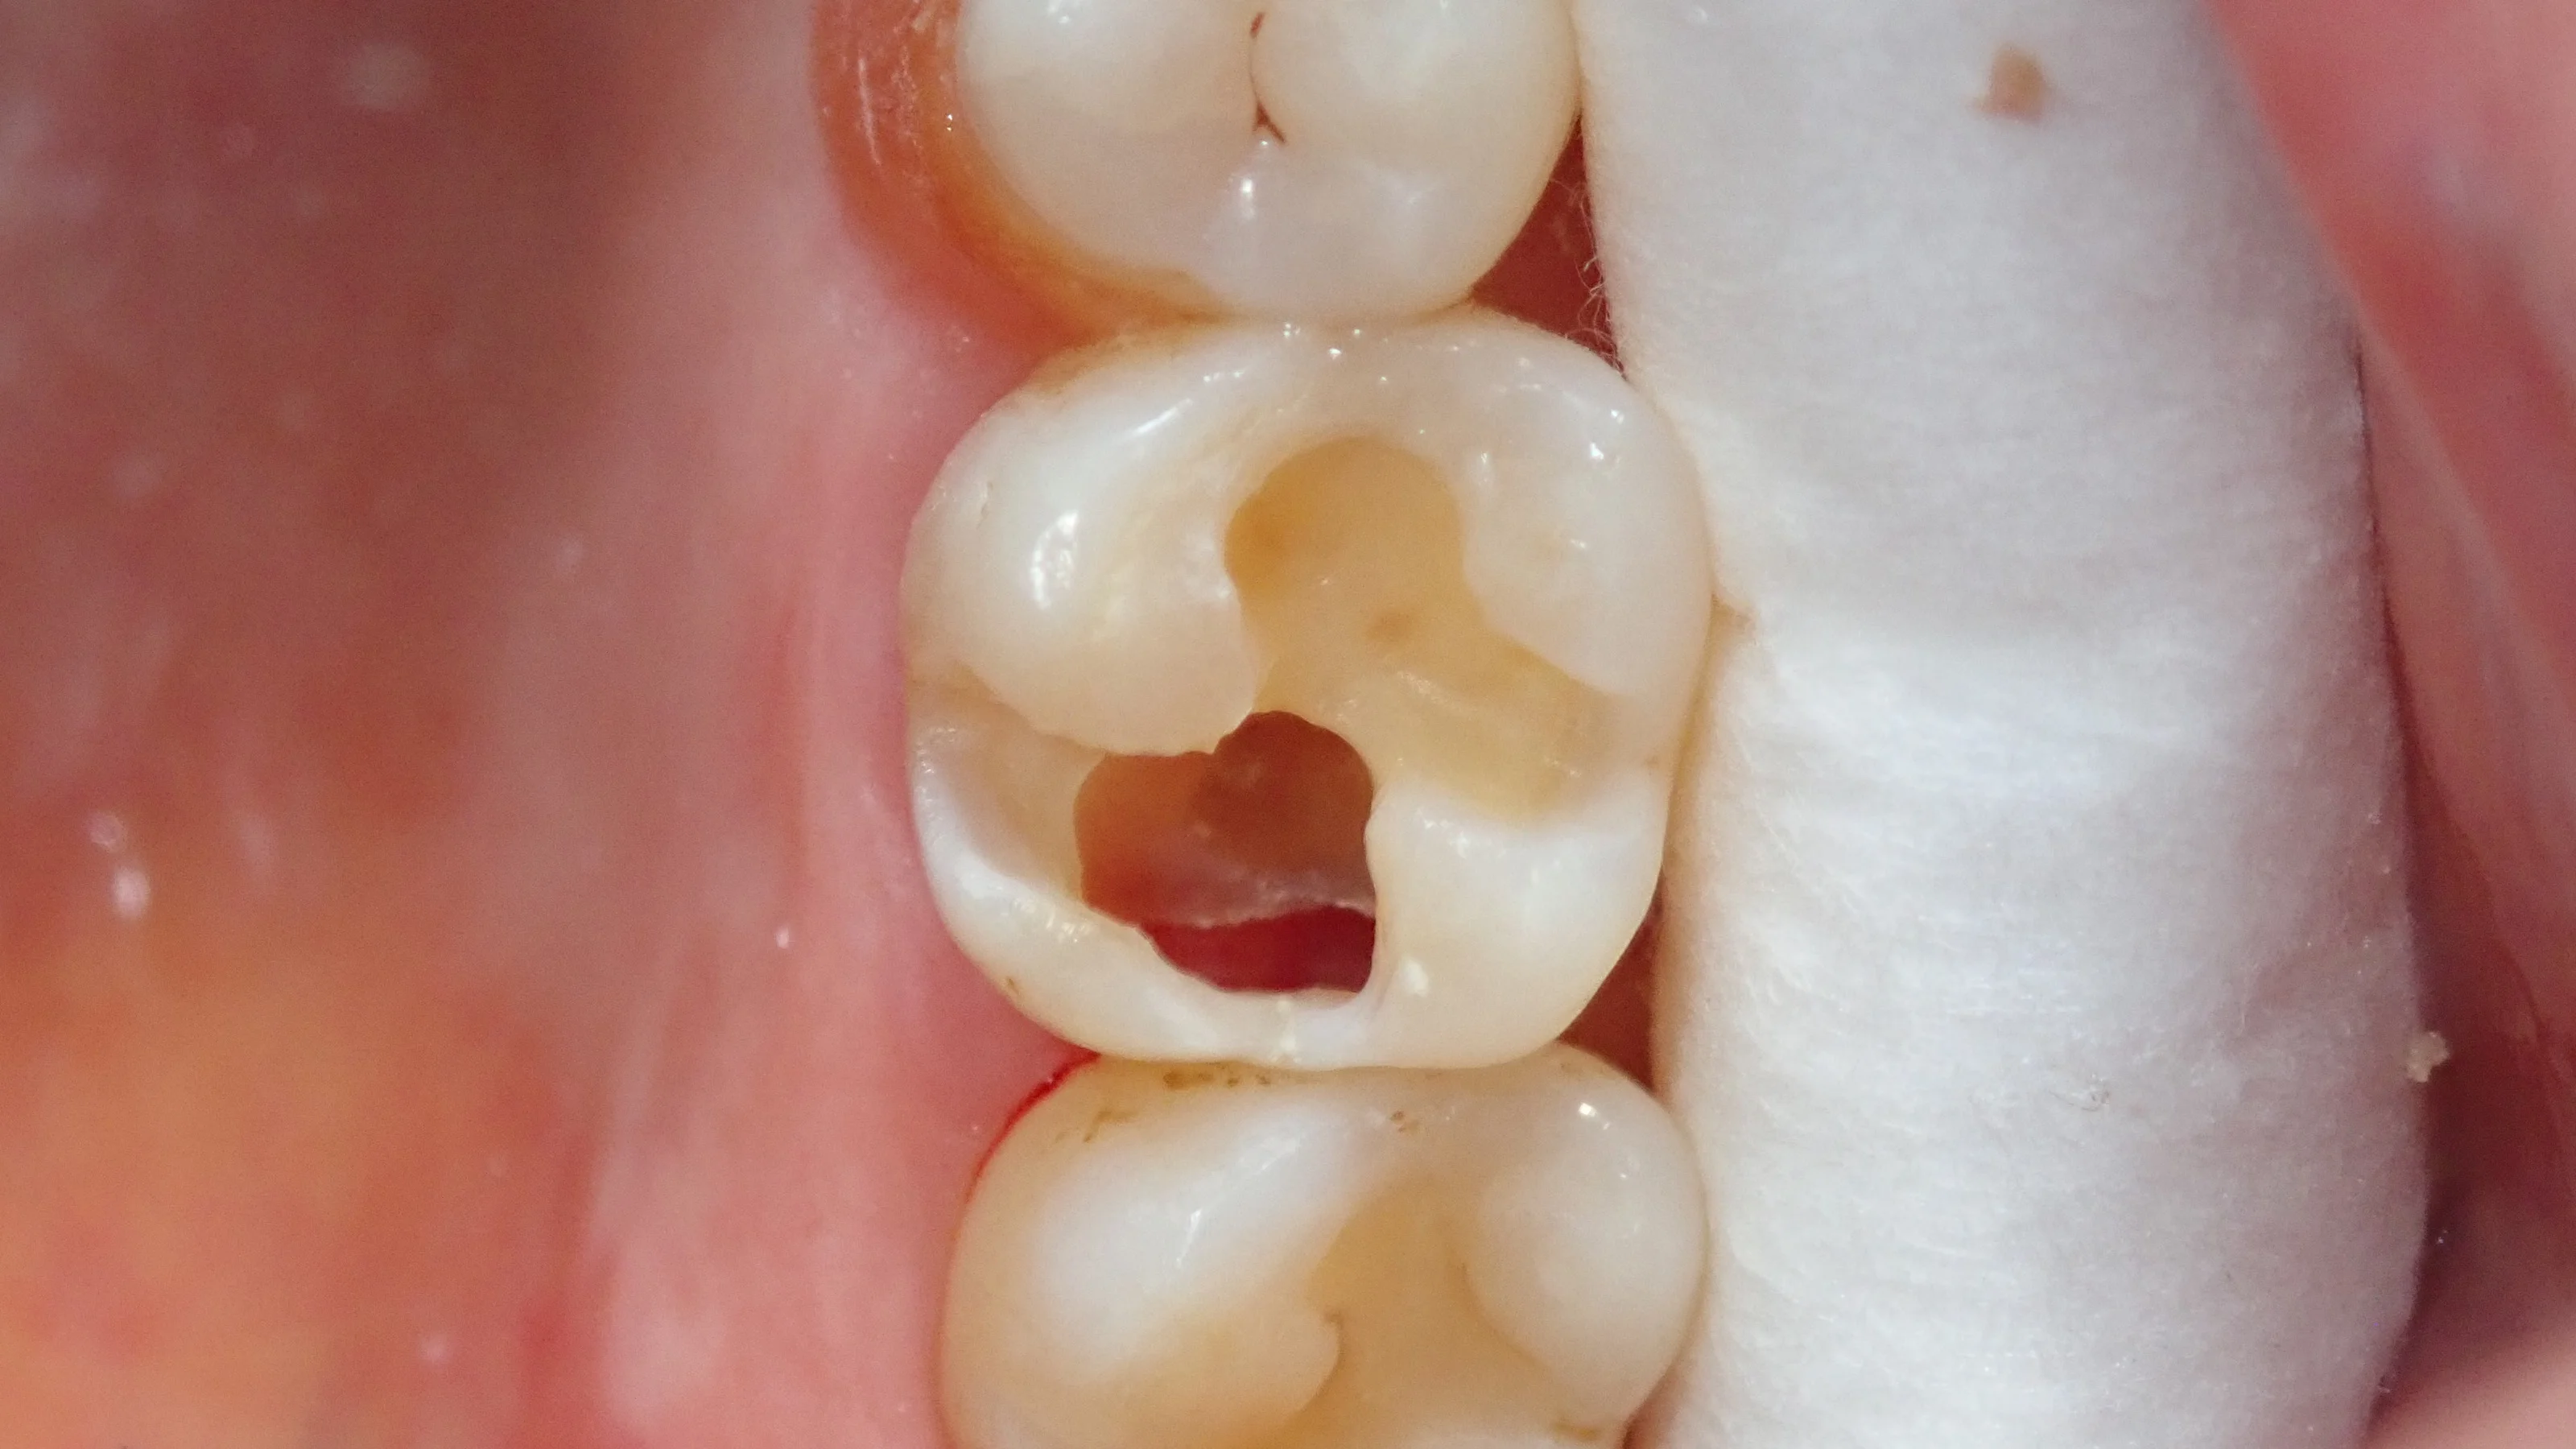

術前です。

白い部分は仮封材 (いわゆる仮の蓋)が入っており、虫歯は既に取り切っている状況です。

そして、仮封材を除去した画像がこちらです。

実際、画像の下半分は中身が殆どない状態です。

神経もうっすら見えており、歯茎が虫歯の穴から見えている状態。

本当にギリギリの状態だったんです・・・。